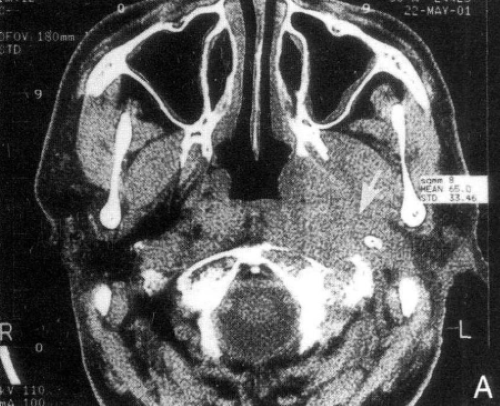

3. Nasopharyngeal MRI (Magnetic Resonance Imaging): The nasopharynx has a concealed location, making it sometimes difficult to examine thoroughly by routine physical examination. MRI can probe the detailed condition of the nasopharyngeal cavity and surrounding tissues, aiding in detecting the presence of a tumor.